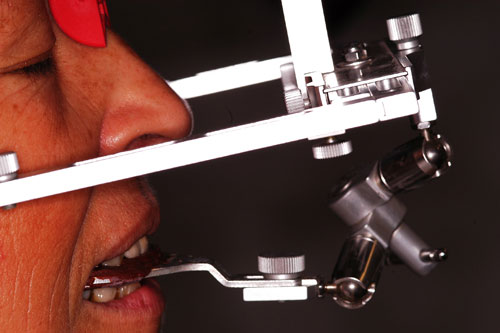

Se aconseja estudio oclusal mediante montaje en articulador semi ajustable.

Registro de Arco Facial ( Para el Montaje del Modelo Sup.)

Registro de Laminillas de Long. (Para el Montaje del Modelo Inf. en O.R.C.)

(Aclaración: estamos usando un articulador totalmente ajustable, como si fuera un semi ajustable).